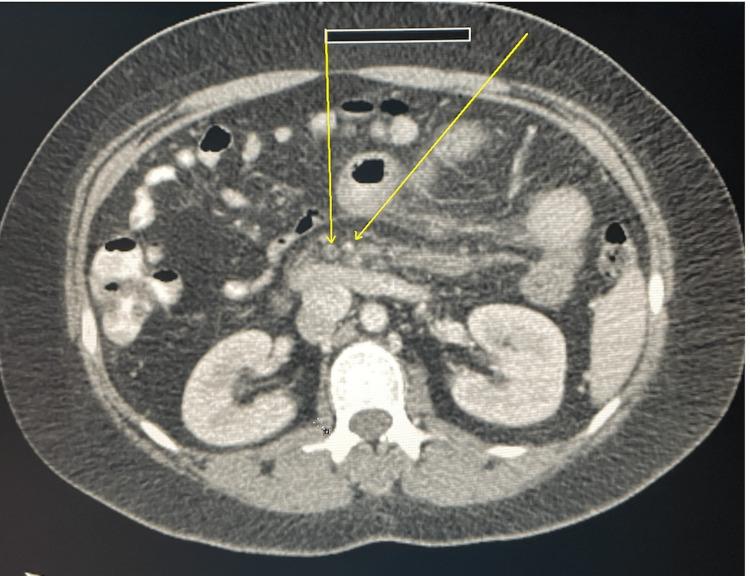

Protein C (PC) is an essential vitamin K-dependent protein that regulates thrombosis and hemostasis in the body. A mutation in the PROC gene on chromosome 2q14.3 results in PC deficiency. The clinical presentation of PC deficiency can vary, ranging from a single vein thrombosis to disseminated intravascular coagulation, purpura fulminans, or even life-threatening complications such as sepsis. Here, we present a case of a 37-year-old female who was found to have acute portal vein thrombosis as an initial presentation of PC deficiency. She presented to the hospital with acute onset of abdominal pain associated with nausea, blood-streaked emesis, and bloody bowel movement.

蛋白C(PC)是一种必需的维生素K依赖蛋白,可调节体内的血栓形成和止血过程。位于2号染色体q14.3区域的PROC基因突变会导致蛋白C缺乏。蛋白C缺乏的临床表现各不相同,从单一静脉血栓形成到弥散性血管内凝血、暴发性紫癜,甚至是败血症等危及生命的并发症。在此,我们报告一例37岁女性病例,该患者最初表现为急性门静脉血栓形成,这是蛋白C缺乏的首发症状。她因突发腹痛伴恶心、呕血带血丝及便血而入院。